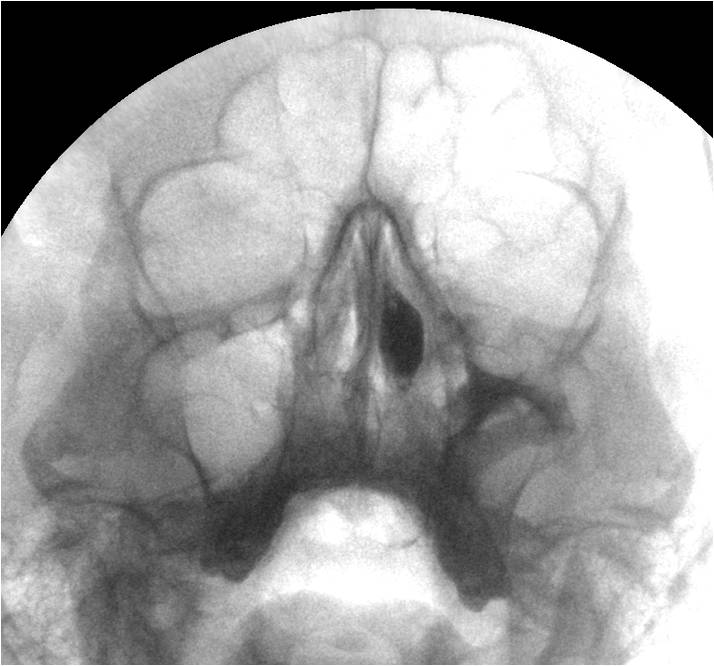

Пример двойной локализации кист правой гайморовой полости - верхне-наружная и передне-базальная...

Приложения:

k8.jpgk88.jpg